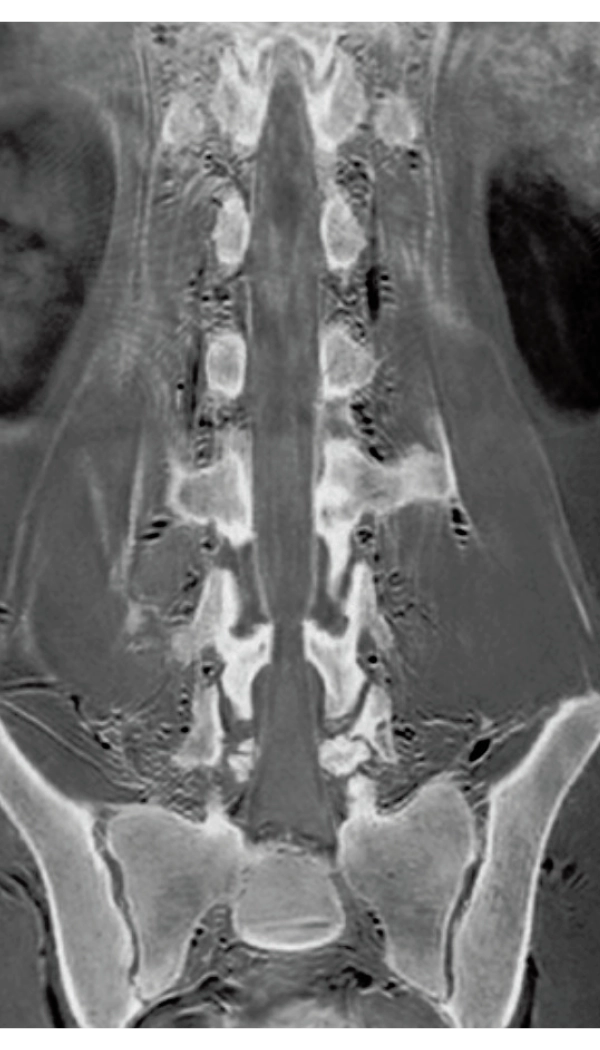

3D Bone

0.93×0.93×1.2(0.6)mm

1.1×1.1×1.2(0.6)mm

3DisoFSE T2WI

0.75×0.75×1.1(0.55)mm

MPR COR